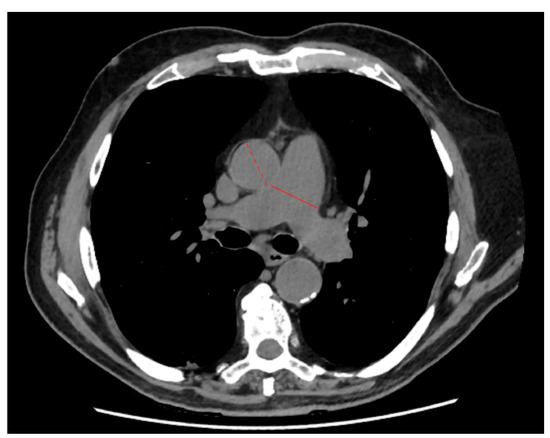

| Vascular features | PA diameter (mm) | Continuous | 28.0 (25.0–30.0) | 28.0 (25.0–30.1) | 28.0 (25.0–30.3) |

| AA diameter (mm) | Continuous | 34.0 (32.0–37.0) | 35.0 (32.0–37.0) | 34.0 (31.0–37.4) | |

| PA/AA ratio | Continuous | 0.81 (0.73–0.89) | 0.81 (0.73–0.90) | 0.81 (0.74–0.89) | |